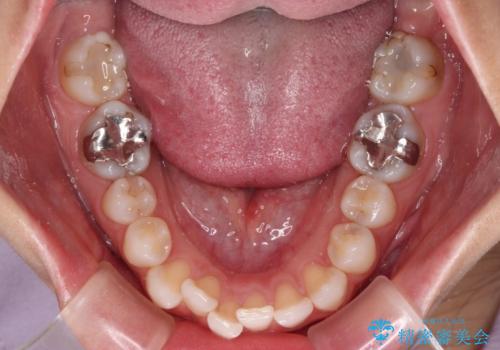

- 歯並びと虫歯をきれいにしたいとのことで来院された患者様です。

楽して短期間で歯列を整えたいとのことで、ワイヤー装置を用いて矯正治療を行い、矯正治療後に下顎の虫歯はセラミックインレー、上顎はPGAインレー(ゴールドインレー)、根管治療を行う歯についてはオールセラミッククラウンにて補綴治療を行うこととしました。

矯正治療は8ヶ月ほどで終了し、速やかに虫歯治療に移行することができました。

保険治療で用いる樹脂(コンポジットレジン)で行った虫歯治療は、周辺が変色して汚くなっていましたが、下顎はセラミックインレーで審美的に、上顎はPGAインレーで歯に負担の少ない治療を行うことができました。